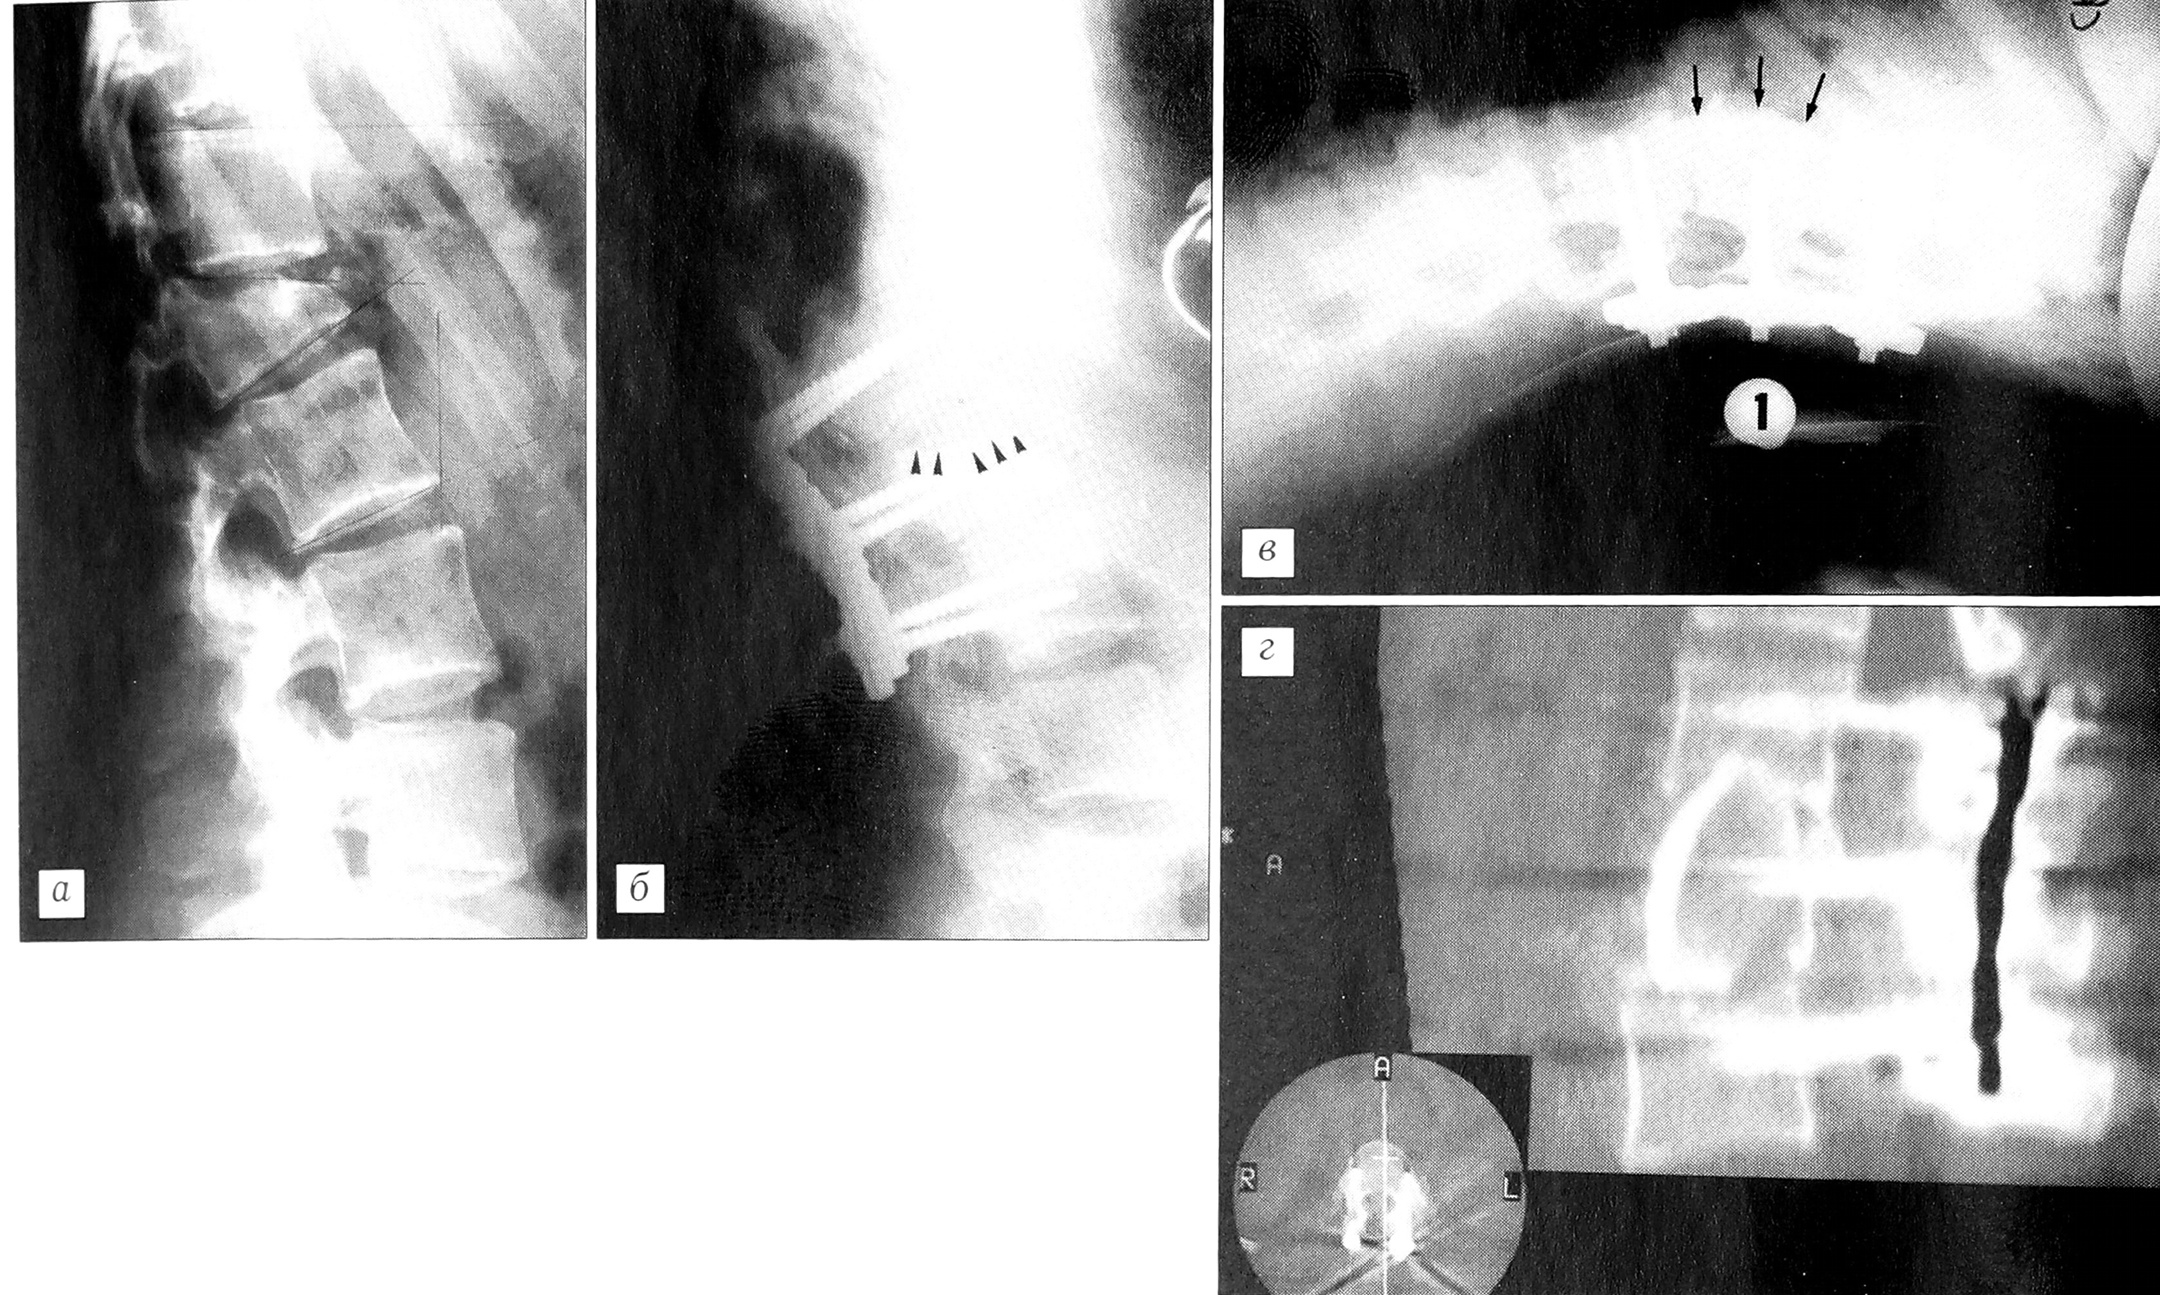

Рис. 7. Перелом L2 с импакцией в вышележащее плато: передний доступ, выполненный после ламинэктомии и репозиции из заднего доступа, с фиксацией транспедикулярной системой. Обратить внимание на положение основы и высоту диска, полученную благодаря трансплантату.а — перед операцией;б — через 6 мес после операции.

Мы произвели 10 корпорэктомий —2 по поводу опухоли и 8 — при травматических повреждениях, в том числе 4 — с целью декомпрессии спинного мозга и 4 — по «механическим» соображениям (рис. 7, 8). Остальным 84 больным произведен передний спондилодез с использованием небольших кортикоспонгиозных трикортикальных трансплантатов (в 9 первых случаях) либо спонгиозных аутотрансплантатов, совмещенных с рассасывающейся основой (в 75 последующих случаях). У 39 больных был выполнен корпородез на одном уровне (у 4 — T12-L1, у 8 — L1-2, у 9 — L2-3, у 6 — L3-4, у 7 — L4-5, у 10 — L5-S1) и у 11 больных — на трех уровнях (у 7 — L2-5, у 4 — L3-S1). У 2 больных установленный ранее металлический имплантат был удален из переднего доступа и заменен трикортикальным трансплантатом. 52 пациента ранее перенесли внутрибрюшные операции.

Рис. 8. Перелом Lie деструкцией тела позвонка.a — рентгенограмма до операции; б — после выполнения коррекции из заднего доступа и ламинэктомии (обратить внимание на неполную коррекцию верхнего плато L1 и на межпозвонковое пространство T12-L1); в — во время операции из переднего доступа — корпорэктомии и установки трансплантата на уровне T12-L2 (обратить внимание на лордоз, достигнутый при помощи поясничного валика — 1); г — послеоперационная сканограмма (контроль).